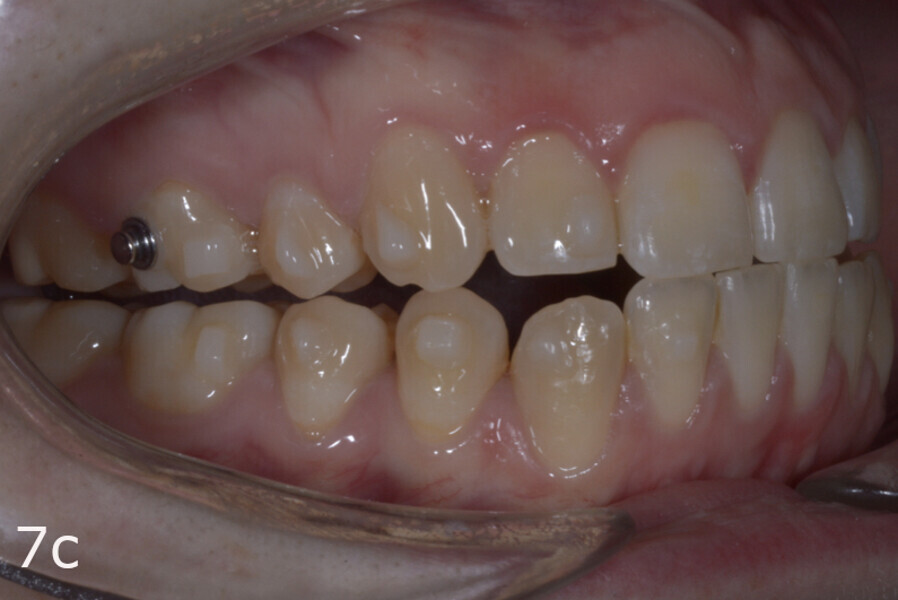

The treatment objectives included closing the anterior open bite, achieving a bilateral Angle Class I relationship and a proper overjet and overbite, correcting the midline discrepancies, and achieving a profile harmonisation. The treatment plan consisted of orthodontic camouflage treatment with asymmetric distalisation in three of the four quadrants using Invisalign aligners (Align Technology) and third molar extraction. The Invisalign Comprehensive package was chosen, and 63 pairs of aligners were used (Figs. 7–10). Each aligner was worn for 20 hours a day for one week each. The use of Class III elastics on both sides was indicated. Afterwards, ten refinement aligners were needed to improve the interdigitation on the right side (Figs. 11 & 12).

Although Class III elastics tend to extrude the maxillary molars and generate clockwise mandibular rotation, aligners allow us to prevent these complications, since we have better control over tooth movement, enabling us to counteract unwanted dental movements. In this case, an intrusion of the posterior teeth was planned, which would generate anticlockwise rotation of the mandible in an anticlockwise direction. This vertical control led to the closure of the anterior open bite and the reduction of the lower facial height, thereby improving the facial profile.

The total treatment time was 15 months. An Angle Class I relationship was established along with adequate anterior and canine guidance, establishing a functional occlusion. This not only ensures optimal masticatory function but also protects the teeth and the temporomandibular joint from excessive force. Maxillary and mandibular fixed retention were installed at the end of the treatment (Figs. 13–19).